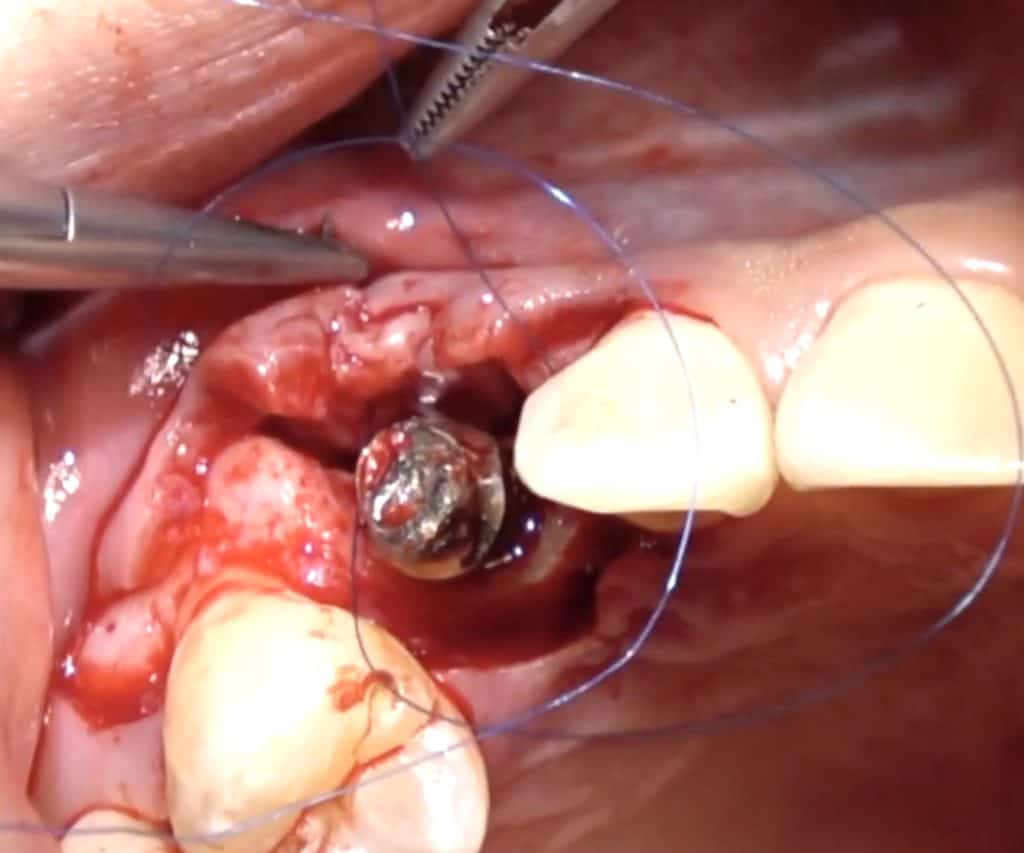

Here is a clinical video of a procedure where the CT-Epithelial graft is applied to create a 2-3 mm zone of keratinised mucosa buccal of an implant crown in the mandible. The graft is harvested from the palate and applied with the procedure explained before

Connective tissue grafts have been also proposed as part pf peri-implantitis surgeries and I think in certain cases they certainly have a purpose to fulfill. I have used the Hybrid CT-Epithelial graft often in peri-implantitis surgery, especially in cases with absence of keratinised mucosa and very thin peri-implant tissue. You can watch such a surgical case in our online Masterclass on the management of implant complications to the right!